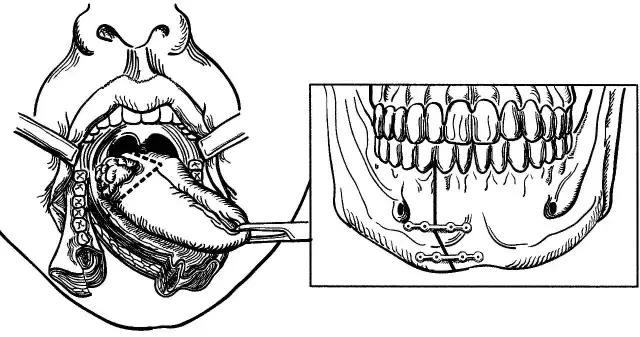

舌癌的经口楔形切除术

下颌骨分段切除术

下颌骨切除术

口腔癌手术路径图